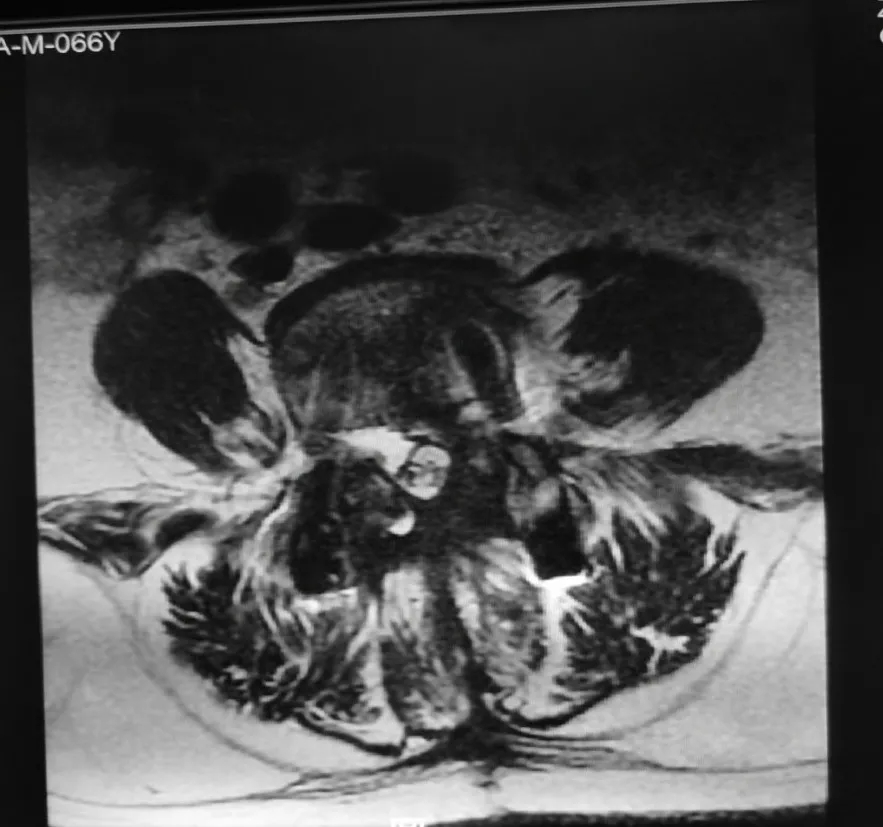

腰椎内固定术后影像:CT可见椎体多个低密度灶。

▲CT

手术操作:2020年6月10日行后路开窗探查术,术中见内固定无明显松动,椎间隙肉芽组织增生,取出深部肉芽组织送检病理微生物鉴定术后,持续冲洗引流1周。病理报告为肉芽组织,细菌培养7天无细菌生长。

骨卫士专家委员会副主席杨述华教授肯定了陈仲教授的诊断及治疗方案。他表示,此病例是一个迟发性的晚期的深部感染,病例的临床症状及影像学有明显的感染迹象,同时C反应蛋白高,陈仲教授通过椎间孔镜取出肉芽组织,进一步证实了病例是感染型。临床上我们提倡能吃药的不打针,能打针的不开刀,能开小刀的不开大刀。陈仲教授的治疗方法很合理,对患者没有造成大的创伤。因为这个患者感染比较严重,涉及到椎体,可能会出现一些或轻或重的疼痛。如果患者出现重度或难以忍受的疼痛,可以选择进一步手术。手术方案可以考虑将后侧螺钉撤掉,前入路做椎体内固定。